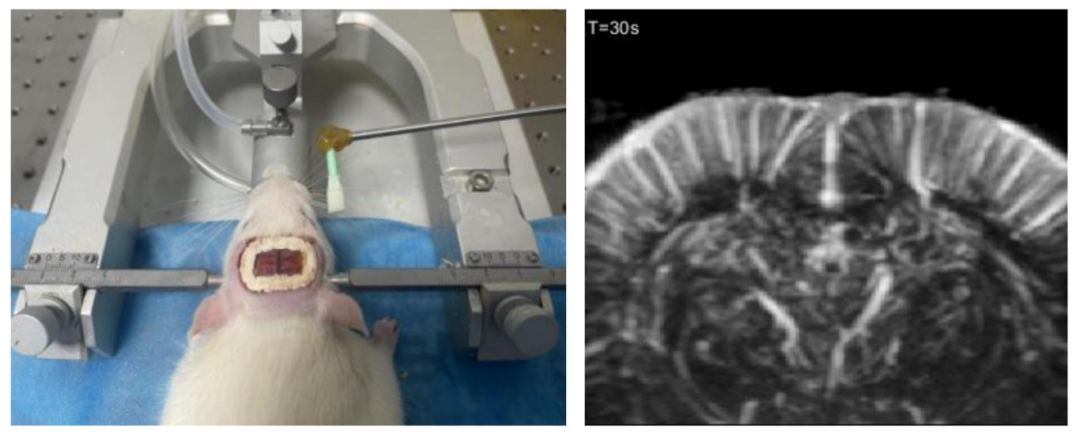

不同于fMRI的分钟级延迟,玉研Sonorover超分辨率成像系统fUS技术以每秒100帧的速度捕捉脑血流动态变化。fUS脑功能超声成像通过超快超声和超灵敏血流成像技术,获取脑部组织微小血流变化,根据神经血管耦合机制,可实时获取脑功能活动状态。

采用周期性刺激大鼠胡须实验,获取大鼠脑区(S1BF)血容量的变化量与触觉刺激的对应关系。

fUS脑功能成像用于追踪清醒大鼠的癫痫发作过程。

UPG100系列动物超声治疗仪可以产生频率、幅度、脉冲长度、重复频率等参数可调的功率脉冲超声波,可应用于超声波无创调控、治疗等动物科学研究,已广泛应用于无创神经调控、靶向给药、血脑屏障开启、声动力治疗、康复治疗、超声溶栓、超声消融等前沿科学实验研究。